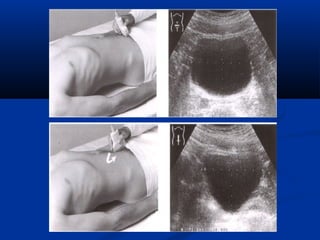

Kyõ thuaät : caùc maët caétKyõ thuaät : caùc maët caét